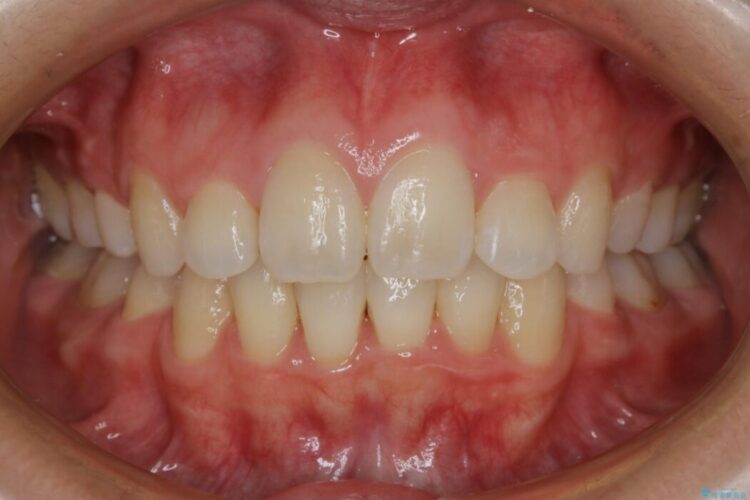

治療後について

顔貌のビフォーアフターでもわかるように口元の出っ張りが改善され、患者様にはとても喜んでいただけました。

横顔であったり笑った時の印象にも変化があるため、同様のお悩みを抱えている方はぜひご相談ください。

本症例の患者様は顎の骨が小さく歯をきれいに並べるための隙間がないため、歯が重なったり傾斜してしまっていました。

抜歯を行うことによりスペースを確保し、小さい骨幅でも歯並びを整えることができます。